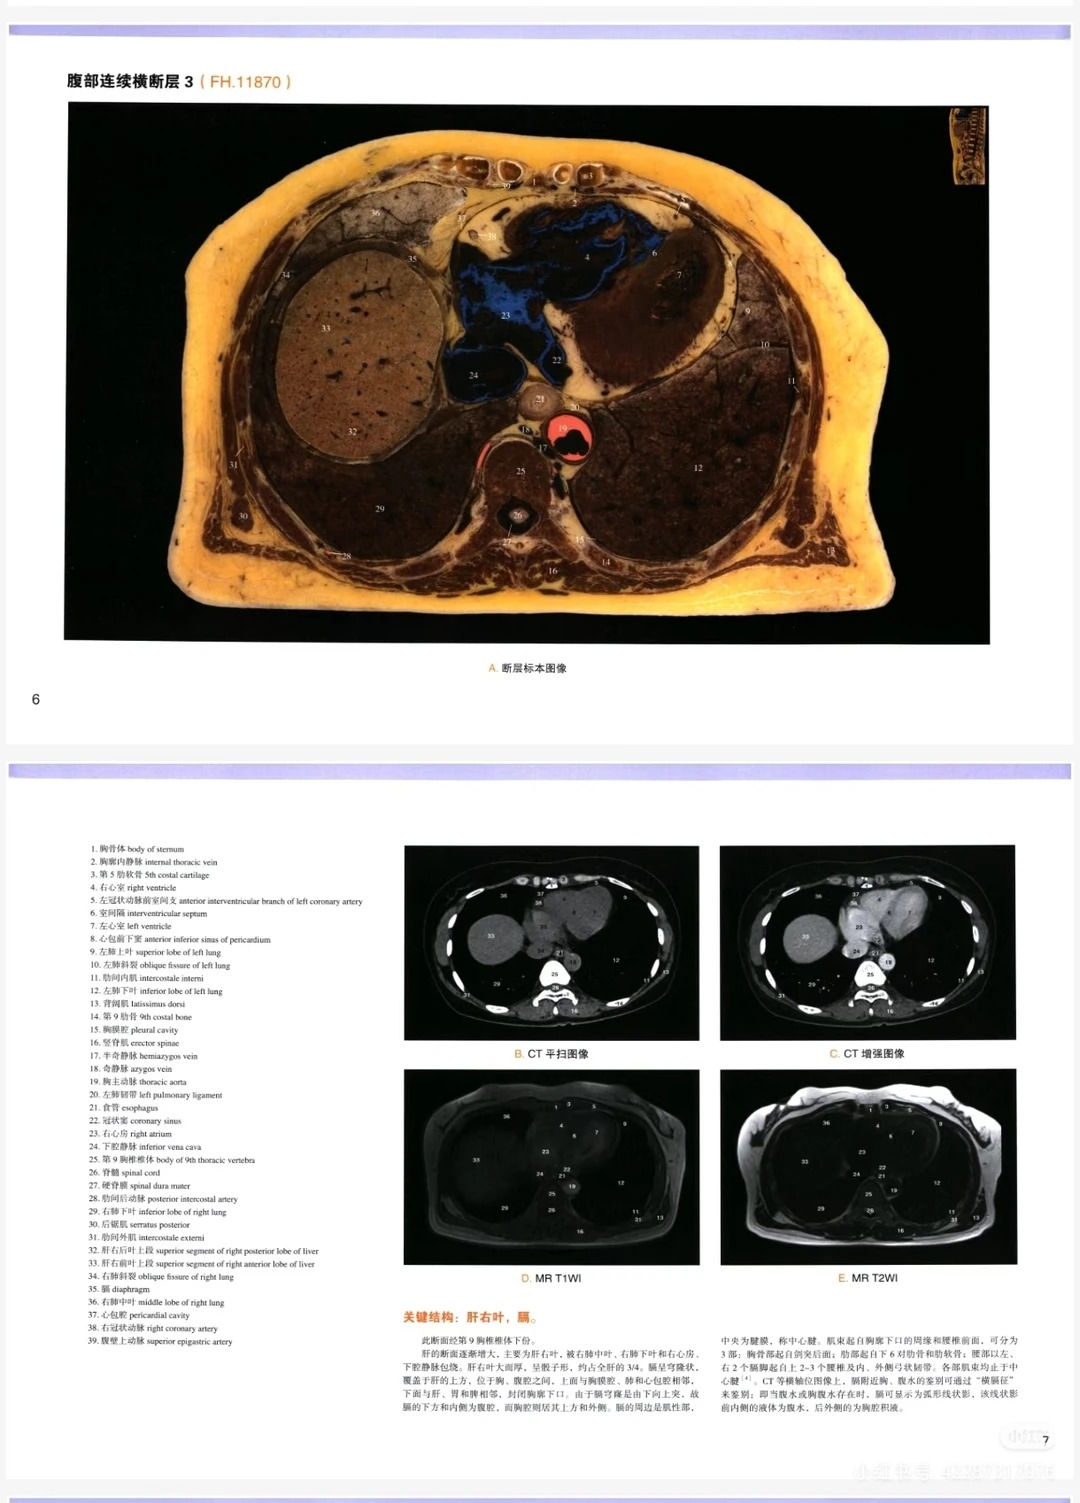

• 超清画质+三重对照,直观易懂:超清断层影像清晰呈现人体每一处细节,搭配3D重建技术和CT/MR实拍对照,将抽象的解剖结构具象化,断层定位、解剖关系一眼看清,就像拥有“人体透视挂”,彻底解决“看不懂、记不住”的痛点。

2. 超清画质+三重对照,学习更高效:超清画质清晰到细节,搭配3D重建和CT/MR实拍对照,直观呈现人体内部结构,断层定位精准,不用凭空想象,帮你快速掌握解剖关系,学习效率翻倍。